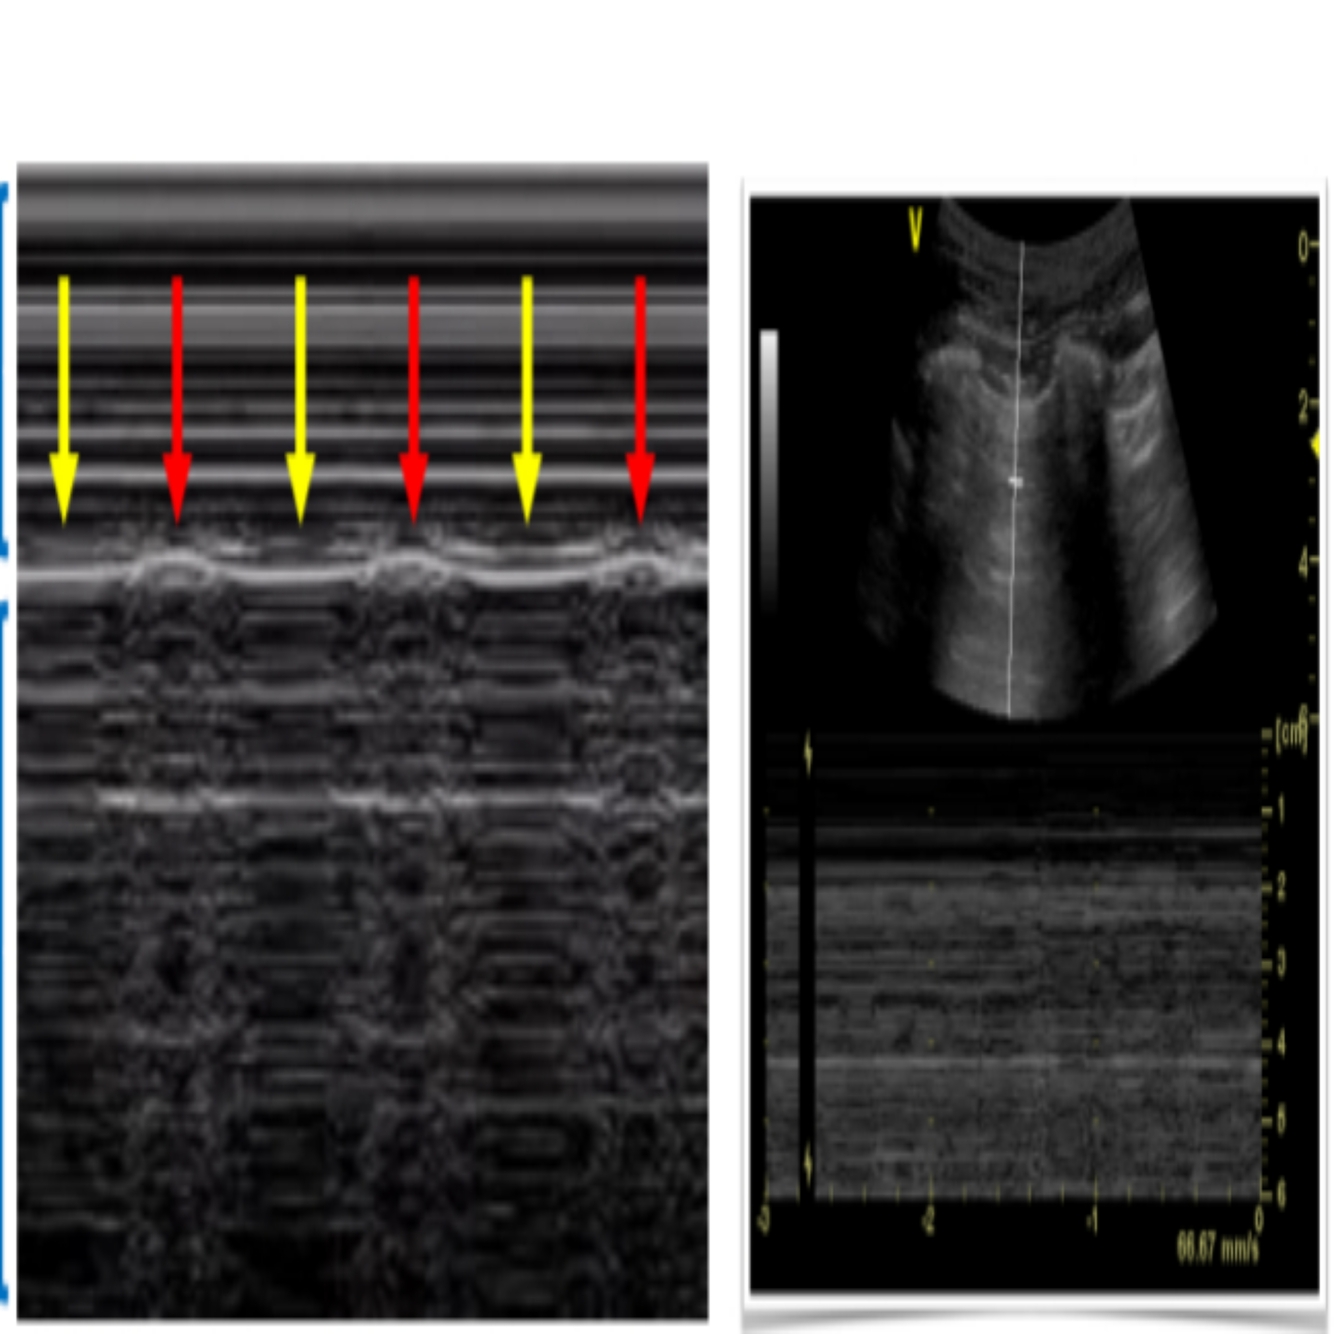

19

Q

POCUS PULMONAR: Qual o nome deste achado?

A

Ponto pulmonar

100% pneumotórax